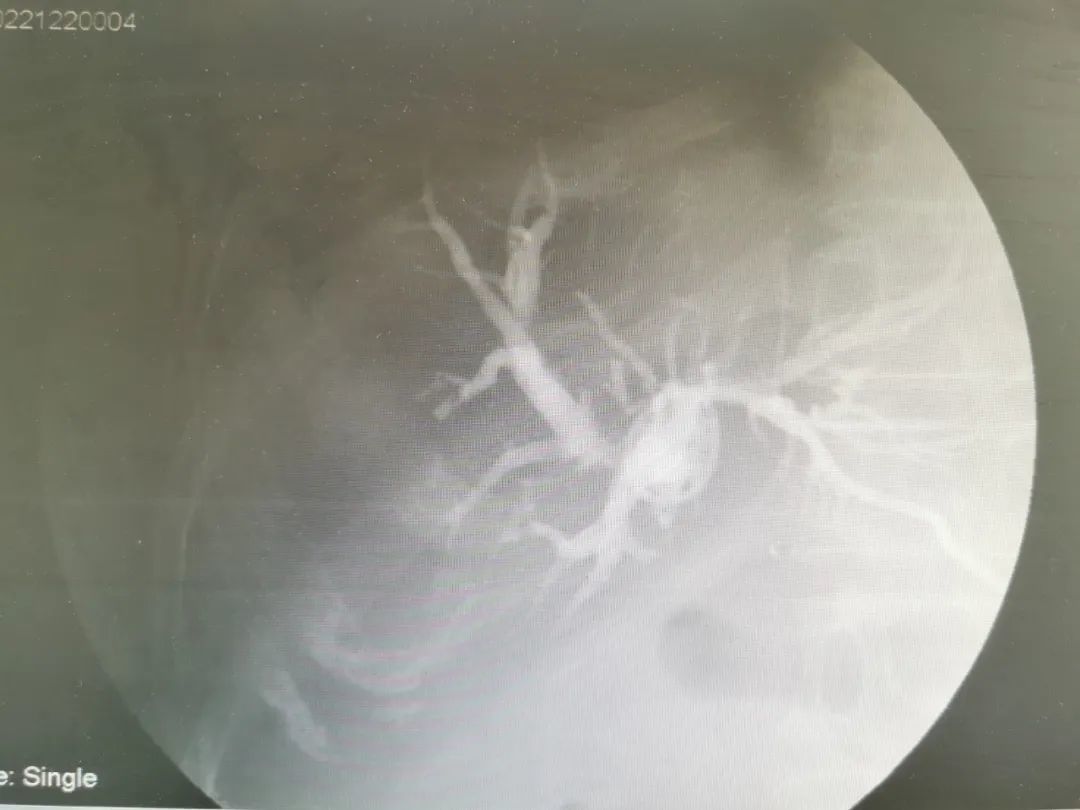

术前

治疗:为患者行胆管内支架植入术。术中经原胆道外引流注入造影剂示肝内胆管扩张,置入超滑导丝交换出原引流管并置入鞘管、造影导管,超滑导丝缓慢开通闭塞段,造影示:胆总管上段、肝总管、肝左、右胆管闭塞。超滑导丝引导下将8mm*60mm胆道支架置入胆管闭塞段,见支架扩张良好,造影剂通过顺利,再将造影导管置于支架内,固定引流管。术后拔除导管,经皮植入胆道支架,恢复解剖通道,患者黄疸、腹痛等症状明显减轻。